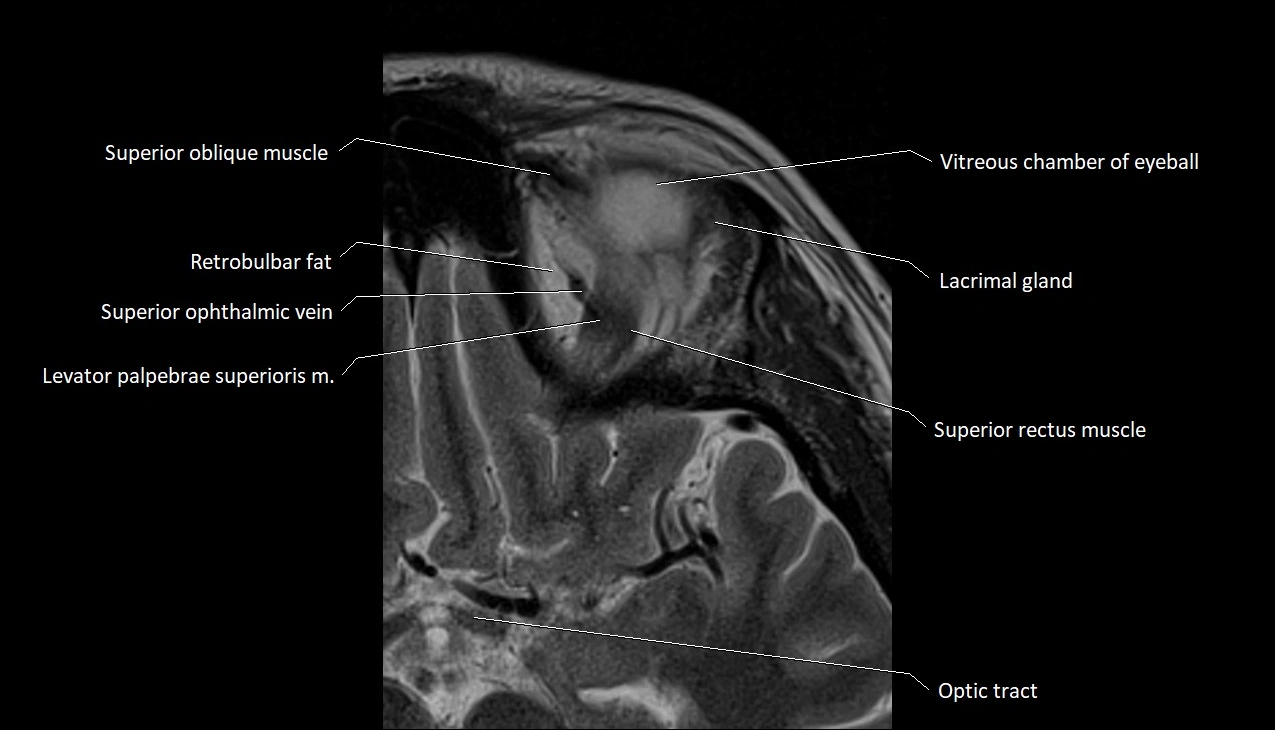

- Superior oblique muscle

- Superior ophthalmic vein

- Superior rectus muscle

- Retrobulbar fat

- Vitreous chamber of eyeball

- Lacrimal gland